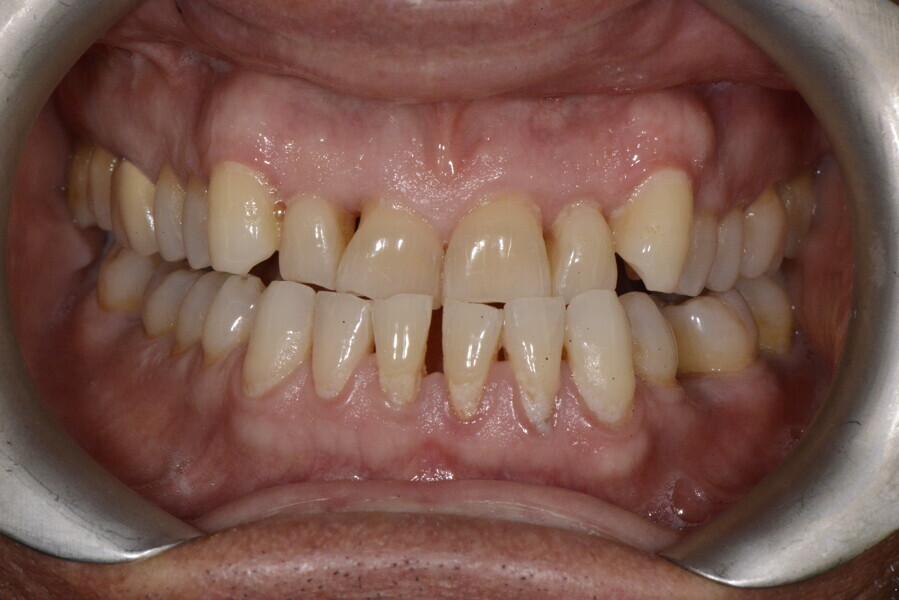

The 58-year-old patient wished to improve his oral aesthetics and function, complaining of mobility of the posterior teeth and wear of the anterior teeth. After data collection, a very complex situation was identified (Figs. 11–13):

1. severe periodontitis with poor prognosis of some teeth;

2. anterior crossbite;

3. severe wear mainly of the anterior teeth and compensatory eruption;38

4. atypical swallowing and lower posture of the tongue at rest;

5. masticatory dysfunction during the mastication test; and

6. no significant signs of temporomandibular disorder.

During the first visit, we checked the centric relation with cotton rolls, eliminating the posterior mesialising precontact and then performed a direct composite aesthetic and functional mock-up in this new position, not only to motivate the patient regarding the final result but also to help him understand better overall why tongue therapy, tooth alignment and dental resurfacing for augmentation of the vertical dimension of occlusion were required (Figs. 14 & 15).